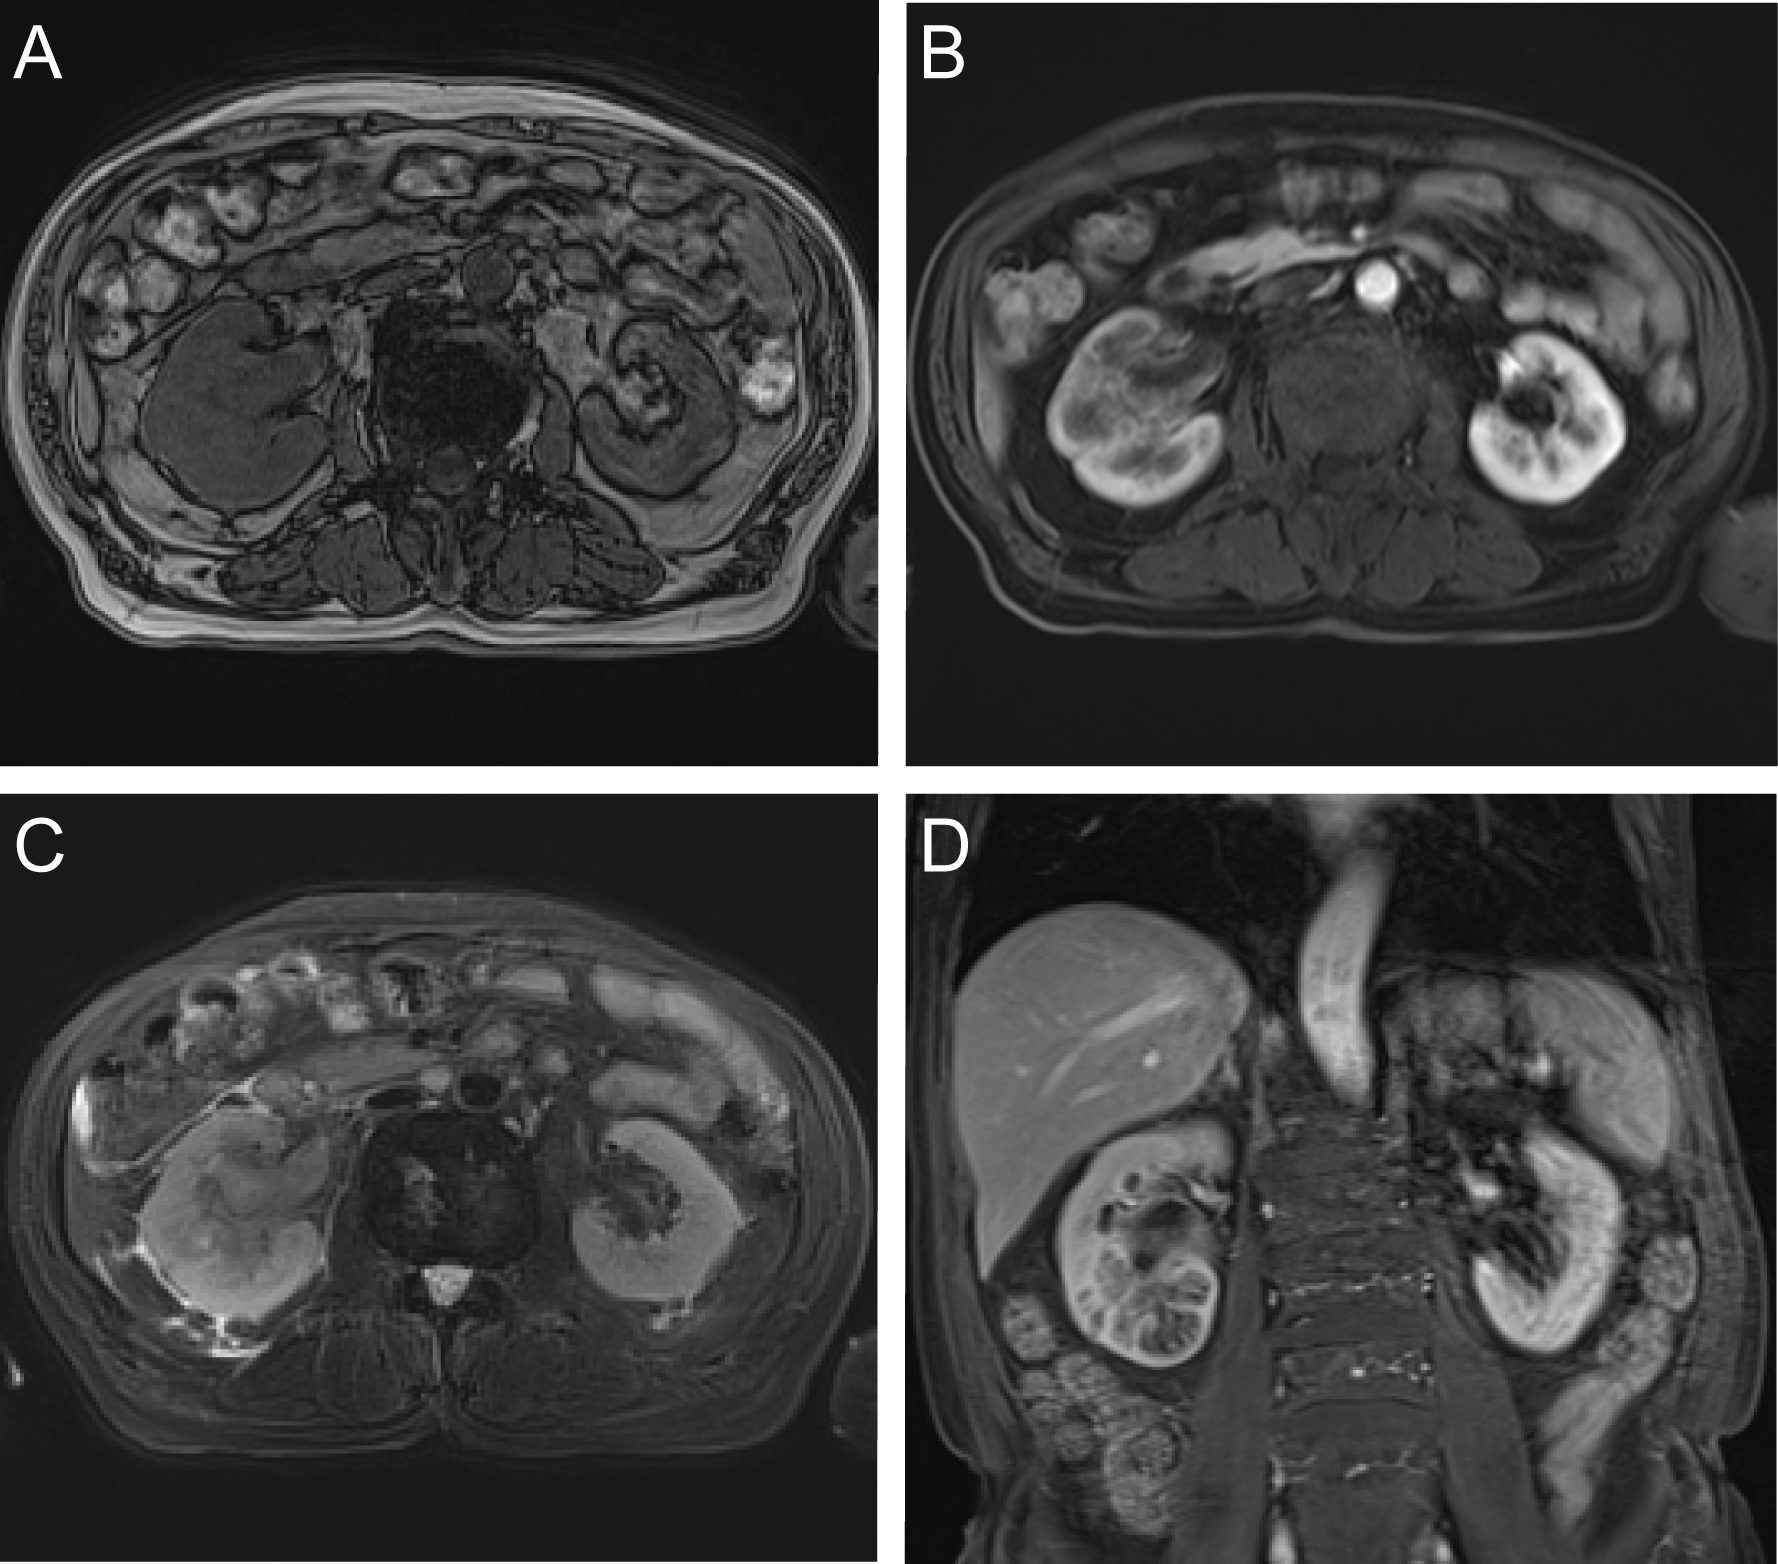

A 71-year-old male reported the development of a fever of no clear origin that rose to 38.5°C beginning 20 days prior to presentation. The fever was mild in the morning and more pronounced in the evening, and was accompanied by nausea, vomiting, dizziness, right-sided back pain, and frequent urinary urgency. Enhanced computed tomography (CT) imaging revealed abnormalities of the right kidney consistent with potential pyelonephritis. Laboratory test results were as follows: white blood cell count 14.79 x 109 cells/L, urine occult blood (UOB) 1+, urinary leukocytes (U-LEU) 3+, erythrocyte sedimentation rate (ESR) 96 mm/h, urine bacterial culture (-), Widal test (-). The patient did not show any significant improvement after anti-inflammatory treatment, and underwent further evaluation at our hospital. Physical examination indicated the presence of positive percussion pain in the right renal area. Enhanced magnetic resonance imaging (MRI) showed multiple irregular mixed signals in the lower and middle parenchyma of the right kidney, with a long T1 low signal on T1WI and a long T2 high signal on T2WI, with marginal circumferential enhancement on enhancement scans. Diffusion-weighted imaging (DWI) showed a high signal and decreased analog-to-digital converter (ADC) values, with marked diffusion restriction of the pelvic wall and parenchymal lesion margins on both DWI and ADC images. The right renal pelvis and calyces were dilated and the right pelvic wall was thickened, with significant enhancement in the arterial phase seen on enhancement scans. Infectious lesions were first considered and a short review in conjunction with clinical treatment was recommended to exclude neoplastic lesions (Figure 1 and Supplementary Figure 1). Laboratory test results at this time were as follows: WBC 22.89 x 109 cells/L; UOB 3+; U-LEU 3+; estimated glomerular filtration rate (eGFR) 96 mL/min. The results of the urine bacterial culture revealed the presence of enterococcus. The patient did not respond to anti-inflammatory treatment, and underwent ultrasound-guided right nephrostomy, which drained 100 mL of pus and provided significant relief of the back pain. The joint consideration of the imaging findings together with the pus drainage provided proof of the presence of a renal abscess. The laboratory findings on the puncture fluid revealed leukocytes (3+) and acid-fast stain (-). Exfoliative cytology analyses of the puncture fluid were performed, and cancerous cells were detected. Anti-inflammatory treatment was maintained for 10 days, and follow-up CT imaging revealed a nephrostomy drainage tube extending from the right renal pelvis to the outside of the body. The right renal pelvis and part of the calyces were dilated, with thickening and enhancement of the wall. The right kidney was less enhanced than the contralateral side. A mass of slight hypointense lesions, approximately 6.3 x 4.6 cm in cross-section, was seen in the lower and middle parenchyma of the right kidney, with mild to moderate heterogeneous enhancement on enhancement scans. The thickening of the right renal pelvic wall was consistent with an infectious lesion, while the abnormal enhancement of the lower and middle portions of the right kidney was thought to correspond with a tumor, suggested in conjunction with the pathology (Figure 2 and Supplementary Figure 2). Following a discussion with the patient and their family, laparoscopic right nephroureterectomy with bladder-cuff resection was performed in our hospital to avoid any further delay in tumor treatment. The patient was transfused intraoperatively with 2 units of erythrocytes and 400 mL of plasma due to preoperative anemia (hemoglobin: 88 g/L). Twenty-four hours after surgery, the patient received a single dose of intravesical chemotherapy (pirarubicin). The gross specimen is shown in Figure 3. Regrettably, we did not photograph the dissected renal pelvis of the specimen, which represents a limitation of our work. The patient recovered well after surgery and was discharged on day 6 postoperatively. Pathology results revealed that the tumor had a biphasic appearance of a high-grade UC and a sarcomatous component with both renal parenchymal and renal sinus fat involvement. Immunohistochemical staining results were P63 (+), CK7 (+), GATA-3 (+), Ki-67+ (60%), P40 (+), epithelial membrane antigen (EMA) (-) and Her2 (0) (Figure 4). According to the American Joint Committee on Cancer (AJCC), the pathological stage was determined to be T3NxMx. The renal function was reviewed 50 days after surgery and showed an eGFR of 91 mL/min, with creatinine and urea nitrogen levels both within normal range. The patient received up to six cycles of treatment with gemcitabine and cisplatin (GC). The renal function was assessed during chemotherapy, showing that the patient tolerated chemotherapy with a mild increase in creatinine. Regular follow-up to date has not revealed any evidence of recurrence or metastatic progression for about 1 year. The treatment flowchart is shown in Figure 5.

Figure 1 Enhanced MRI examination. (A) axial T1-weighted imging; (B) axial T1-weighted arterial phase imaging; (C) axial T2-weighted imging; (D) coronal T1-weighted arterial phase imaging.